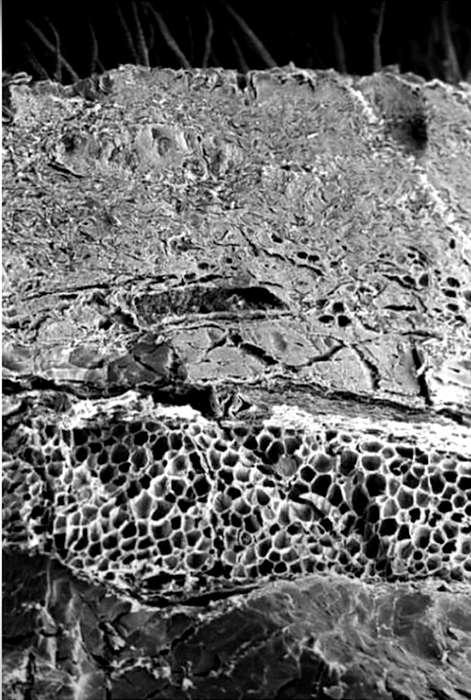

Клетки, расположенные по соседству с основным слоем надкожицы, по виду как будто ничем не отличаются от нормальных, но глаз специалиста сумеет подметить в них первые признаки начинающегося разрушения. Более старые клетки, раньше отделившиеся от клеток основного слоя и находящиеся ближе к поверхности кожи, успели сильно измениться. Они стали более плоскими, их вещество переродилось, сделалось похожим на то, из которого состоят человеческие ногти, волосы или рога и копыта животных. Самые старые клетки, расположенные в верхних слоях надкожицы, уже окончательно погибли и ороговели. Такие отмершие клетки, едва заметные под микроскопом, как бы склеиваются друг с другом и постепенно слущиваются с поверхности кожи, они, как тяжёлые доспехи средневекового рыцаря, принимают на себя все удары и сохраняют невредимыми живые клетки основного слоя надкожицы.

Под плотным слоем живых клеток надкожицы находится «собственно кожа» толщиной 1-2 мм, в ней гораздо меньше клеток, и расположены они на значительном расстоянии друг от друга, пространство между клетками заполнено особым волокнистым веществом, которое придаёт коже упругость, множеством кровеносных сосудов, тончайших нервных веточек, волосяные фолликулы, сальные и потовые железы, выходы чувствительных нервных окончаний. Так, раздражение одних нервных окончаний вызывает ощущение боли, других — ощущение давления, третьих - ощущение прикосновения. Особенно сложно строение нервных окончаний, чувствительных к холоду и теплу. При внимательном рассмотрении можно заметить, что окончания некоторых нервных веточек проникают в надкожицу, образуя так называемые «биологически активные точки».

В глубоких слоях кожи количество упругих волокон постепенно уменьшается, ткань становится более рыхлой, в ней появляются жировые клетки. Сначала они расположены поодиночке или отдельными маленькими группами, затем их становится всё больше и больше, и, наконец, они заполняют всю ткань. Кожа переходит в подкожную, или жировую, клетчатку, толщина которой в некоторых местах достигает нескольких сантиметров.